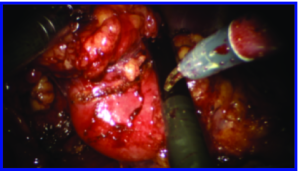

Appearance is one of the most important visual cues to distinguish between different structures in an image. Appearance is described by studying the distribution of different features such as intensity values in gray-scale images, color, and texture inside each object. In most cases, appearance models are incorporated into the data term in (2) and (7). The purpose of incorporating appearance prior is to fit the appearance distribution of the segmented objects to the distribution of objects of interest, e.g. using Gaussian mixture model (GMM) (Rother et al., 2004). In the literature, there are two ways to model the appearance: 1) adaptively learning the appearance during the segmentation procedure, and 2) knowing the appearance model prior to performing segmentation (e.g. by observing the appearance distribution of the training data). In the former case, the appearance model is learned as the segmentation is performed (Vese and Chan, 2002) (computed online). In the second case, it is assumed that the probability of each pixel belonging to particular label is known, i.e. if represents a particular set of feature values (e.g. intensity/color) associated with each image location for object, then it is assumed that is known (or pre-computed offline). This probability is usually learned and estimated from the distribution of features inside small samples of each object. Figure 9 illustrates the probability of different structures (the kidney, the tumour, and the background) in an endoscopic scene. A lower intensity in Figures 9(b-d) corresponds to higher probability.